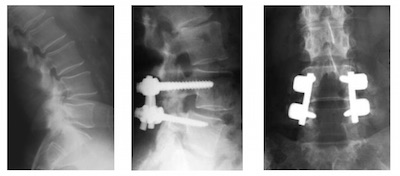

spondylolisthesis dégénratif

Spondylolisthesis L4L5- Vue pré et postopératoire avec le matériel